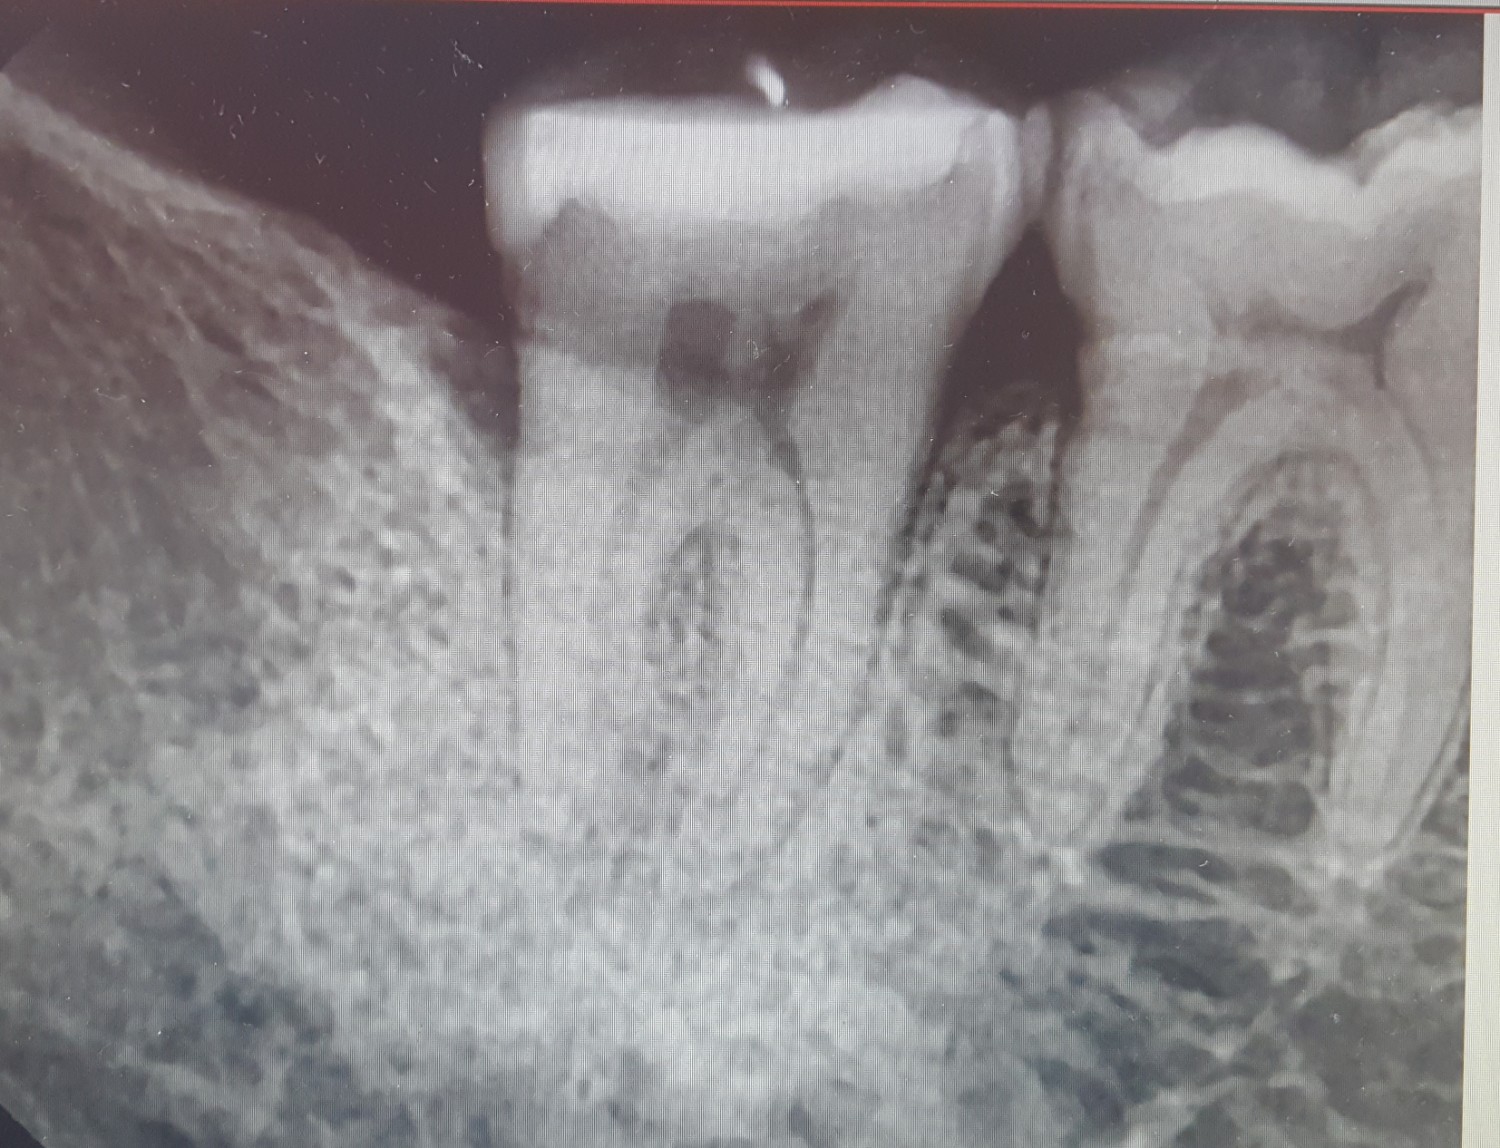

เอซเรย์ฟันมา รบกวนคุณหมอดูให้หน่อยค่ะ

ดูให้หน่อย ฟันซี่ซ้าย (อุดไปเมื่อเดือนที่แล้ว) คุณหมอที่เอกเรย์ บอกฟันเป็นปกติ แต่เราเสียวฟันกินน้ำร้อน เย็น และเคี้ยวอาหาร ปวดจนต้องกินยา